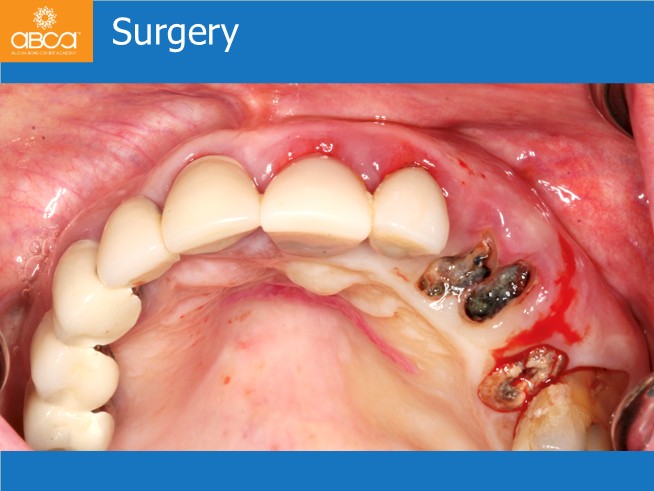

The oral exam shows lacking bone around the top, left, canine and first premolar. Advanced periodontal disease around the top, left incisors with gingival inflammation and poor aesthetics. The patient’s hygiene was very poor.

Complimentary exams confirmed the loss of periodontal bone on the left maxilla, and the need for total rehabilitation in the top left site. The patient was nervous and did not want to extract the first molar at this time.

Treatment plan includes extraction of the teeth and roots from #21 (9) to #25 (13). Without opening a flap, placement of 3 immediate implants for an immediate bridge with 5 teeth. Placement of the final Nobel Procera bridge 6 months post-op.